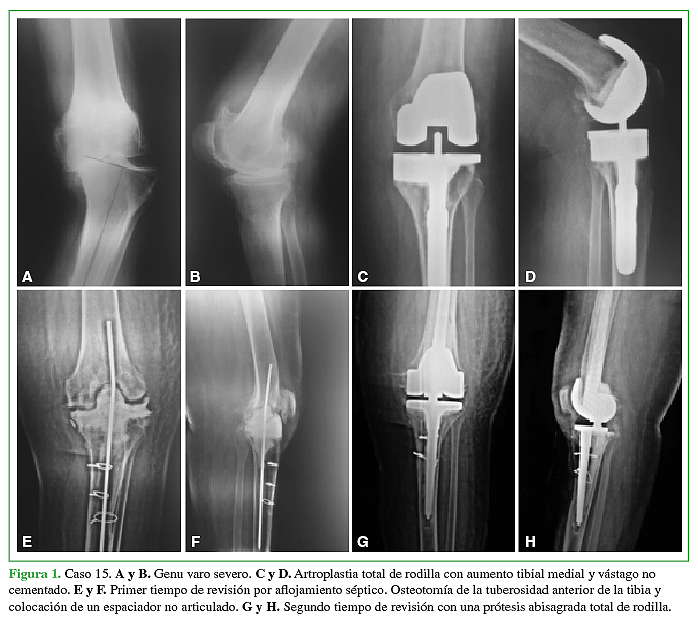

Introducción El objetivo del trabajo es presentar los resultados clínicos y radiológicos a mediano plazo de 34 artroplastías totales de rodilla abisagradas-rotatorias. Materiales y Métodos Estudiamos un grupo de 34 prótesis abisagradas de rodilla. La indicación de una bisagra fue en 10 casos (29.5%) en el escenario de una cirugía primaria y en 24 casos (70.5%) en el escenario de una cirugía de revisión. La edad promedio de la serie fue de 78.5 años (rango de 54 a 85). Resultados El seguimiento promedio fue de 6.5 años (rango de 2 a 12 años). El rango de movilidad conseguido fue 110º de flexión (rango de 70º – 130º) y 5º de extensión (rango de 0º a 20º). El puntaje promedio en el KSS mejoró de 38 en el preoperatorio a 82 en el postoperatorio. En la evaluación radiológica detectamos en 8 (23%) casos líneas radiolúcidas > a 2mm alrededor del componente femoral y/o tibial o alrededor de los vástagos. Cinco de 34 prótesis (14.7%) presentaron complicaciones. En 3 casos (8.9%) se trató de una infección profunda. Dos casos (5.9%) presentaron complicaciones patelo-femorales. La sobrevida de la prótesis libre de revisión a los 6.5 años fue de 94%. Si consideramos el aflojamiento aséptico como causa de revisión la sobrevida fue del 100%. Conclusión Las prótesis abisagradas rotatorias de rodilla modernas presentan buenos resultados funcionales y de alivio del dolor. También se asocian a bajos índices de aflojamiento aséptico a mediano plazo. Sin embargo, las complicaciones sépticas son frecuentes.Descargas